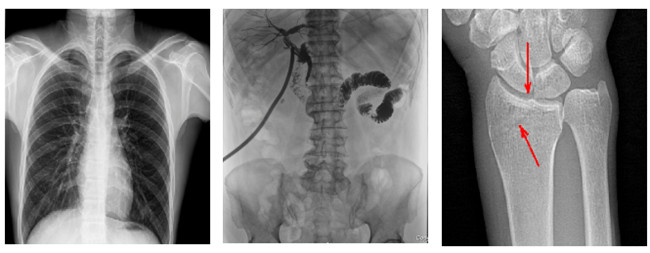

普利德多功能懸吊動態DR,搭載100μm高品質動態平板探測器,不僅滿足常規的數字化X線全身攝影需求,同時還擁有數字攝影、數字透視、數字造影、全景拼接等多種功能,極大地拓展了X線檢查在臨床應用范圍,為醫院臨床應用帶來更多實用價值。基于百微平板的高清成像,圖像清晰度與分辨率更高,可滿足不同檢查部位對細節成像的高品質要求,在胸腹部、脊柱等復雜骨骼和軟組織的攝片上應用,更便于觀察隱匿性病灶,精準識別疑難病癥。

不同于靜態DR拍攝隱匿性病灶時,由于組織重疊病灶難辨,耗費時間更長且易漏診、誤診,普利德多功能懸吊動態DR可通過動態實時連續成像,對于重疊部位病灶或者易被遮擋的病灶進行多角度動態觀察,毫秒級時間內實現動靜態轉換點片,快速、精準完成攝片。比如隱匿性肋骨骨折,可在透視下觀察患者的呼、吸過程,避開重疊影像,快速點片,保證檢查部位的病癥不被遺漏,實現精準診斷。